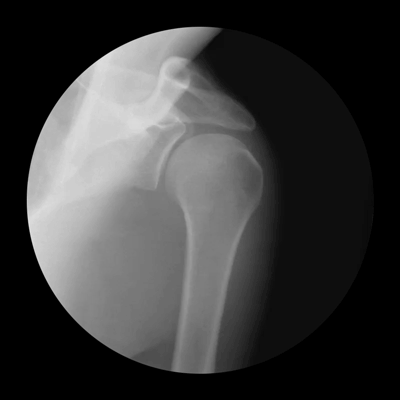

Shoulder